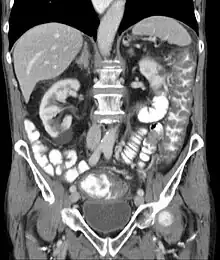

![]() | |

| Pathological specimen showing pseudomembranous colitis | |